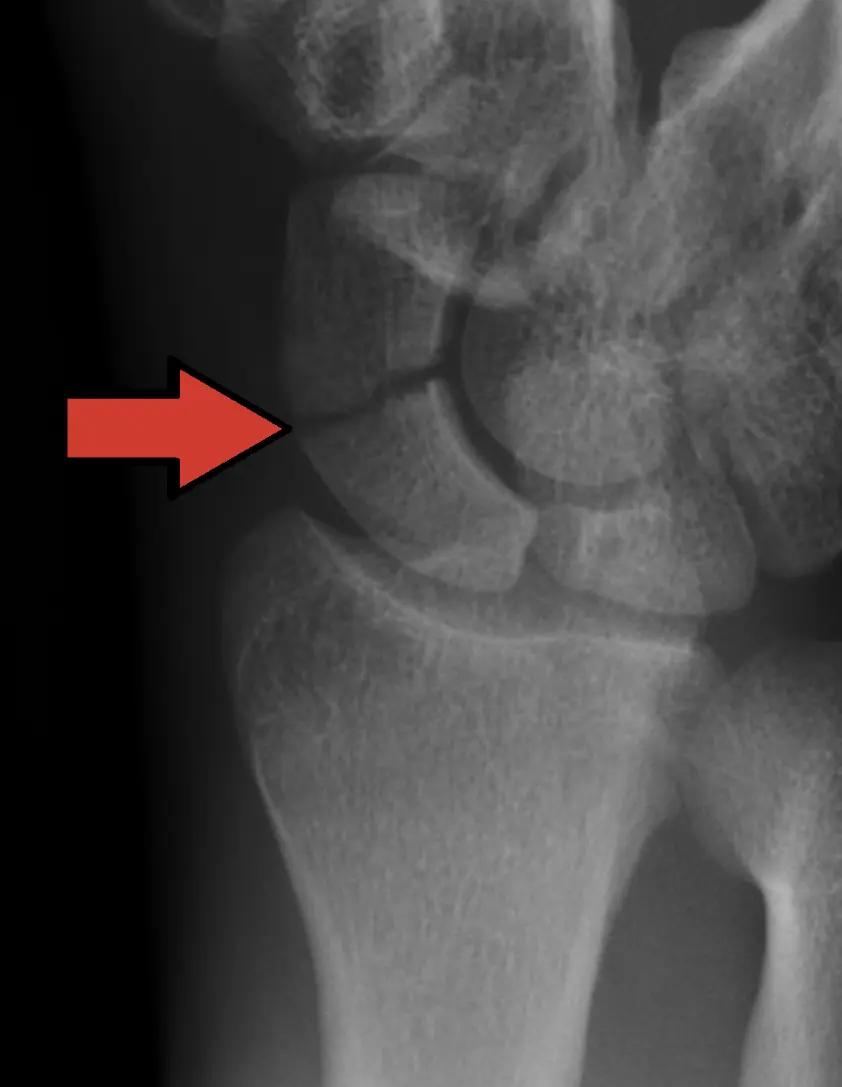

2. بېغىش قىيىقسىمان سۆڭەك سۇنۇش: يوشۇرۇن خەتەر

بېغىشتىكى قىيىقسىمان سۆڭەك (Scaphoid) كىچىك بولسىمۇ، ئەمما ئۇنىڭ رولى ئىنتايىن مۇھىم. بۇ سۆڭەك سۇنغاندىن كېيىن، كۆپىنچە كىشىلەر ئۇنى ئادەتتىكى بېغىش تارتىشىپ قېلىش دەپ ئويلاپ سەل قارايدۇ. چۈنكى دەسلەپكى رېنتىگىن نۇرىدا سۇنۇق سىزىقى بەزىدە ئېنىق كۆرۈنمەسلىكى مۇمكىن.

بۇ سۆڭەكنىڭ ساقىيىشى تەس بولۇشتىكى سەۋەب شۇكى، ئۇنىڭ قان بىلەن تەمىنلىنىشى «تەتۈر يۆنىلىش»لىك بولىدۇ. يەنى قان تومۇرلار سۆڭەكنىڭ ئالدى تەرىپىدىن كىرىپ كەينىگە قاراپ بارىدۇ. سۇنۇق يۈز بەرگەندە، سۆڭەكنىڭ بىر قىسمىنىڭ قان بىلەن تەمىنلىنىشى پۈتۈنلەي ئۈزۈلۈپ، سۆڭەك نېكروزلىنىش كېلىپ چىقىدۇ. ئەگەر بالدۇر دىئاگنوز قويۇلۇپ، گەج بىلەن چىڭ تۇتۇلسا ياكى زۆرۈر تېپىلغاندا ئوپېراتسىيە قىلىنسا، ئەسلىگە كېلىش ئۈمىدى بار، ئەكسىچە بولغاندا قول بوغۇمىنىڭ ئىقتىدارى مەڭگۈلۈك زىيانغا ئۇچرايدۇ.